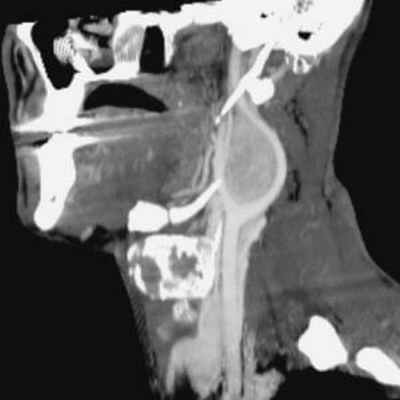

По данным МРТ головного мозга с усилением сигнала парамагнетиком выявлена опухоль парастволовой локализации справа, компримирующая продолговатый мозг и исходящая из расширенного канала подъязычного нерва. Меньший по размерам компонент опухоли располагался в полости канала и распространялся экстракраниально (рис. 1). Рис. 1. МРТ головного мозга пациентки В. до операции. При усилении сигнала выявляется опухоль справа, соответствующая невриноме, в форме «гантели», располагающаяся одной частью на уровне краниовертебрального перехода и вызывающая компрессию ствола мозга, а другой — частью в костных структурах.

При СКТ головного мозга в костном режиме выявлен расширенный канал подъязычного нерва с деструкцией его стенок. Заднелатеральная стенка практически отсутствовала, вследствие чего полость канала сообщалась с просветом яремного отверстия (рис. 2). Рис. 2. СКТ головного мозга пациентки В. в костном режиме до операции. Определяется деструкция канала подъязычного нерва справа, канал отделен от полости яремного отверстия тонкой костной перегородкой (указано стрелкой).

Пациентке выполнена операция по удалению опухоли. В положении «конкорд» (лежа на операционном столе лицом вниз) произведен срединный субокципитальный доступ с резекцией задней дужки позвонка СI и чешуи затылочной кости с латерализацией трепанационного окна вправо. Твердая мозговая оболочка рассечена дугообразно над правой гемисферой мозжечка и стволом мозга до позвонка СII и фиксирована на лигатурах. Вскрыта арахноидальная оболочка большой затылочной цистерны, полушарие мозжечка отведено при помощи шпателя, обнаружена опухоль светло-желтого цвета с капсулой и небольшим количеством сосудов на ее поверхности, исходящая из боковой части большого затылочного отверстия. При нейрофизиологическом мониторинге черепных нервов на нижней и передней поверхностях определено расположение корешков отводящего нерва и корешка СI.